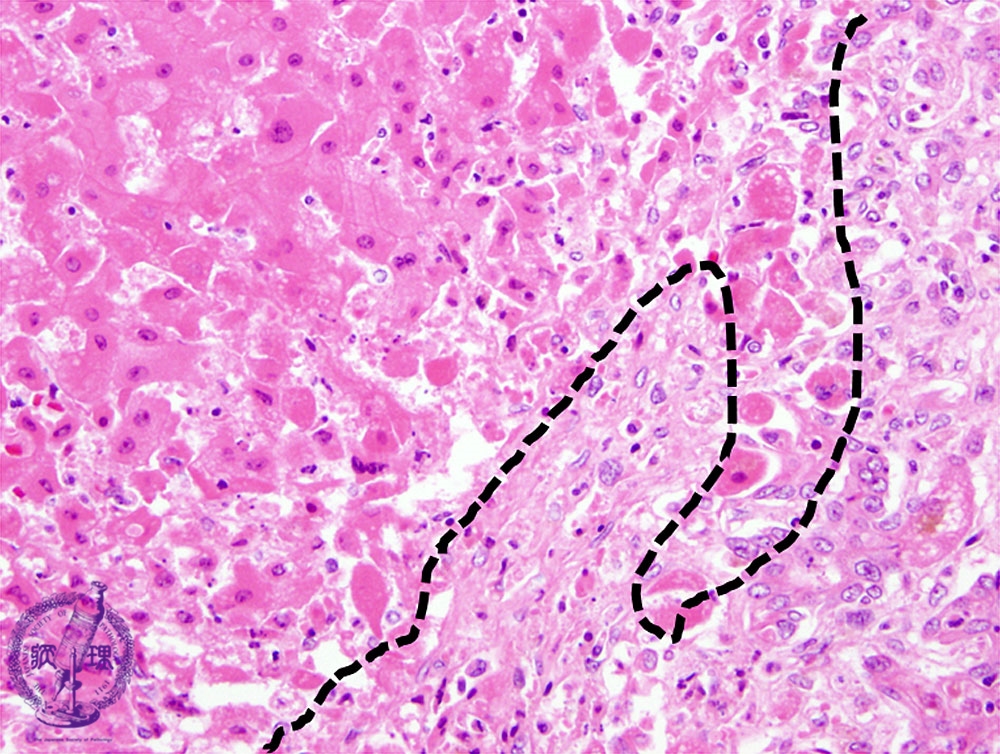

- ★(3)Fulminant hepatitis

Microscopic image (HE stain, high power): There is an interface between necrotic (left of the dotted line) and non-necrotic areas; the necrotic hepatocytes are swollen and more eosinophilic.